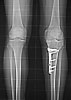

Freitag, 12. August 2005, 09.45 Uhr: Röntgenbilder

Röntbenbild 11.8.2005 - klicken für grösseer FassungGute Neuigkeiten: Endlich von den Schläuchen und diesem sehr praktischen Infusionsständer befreit! Das erste Mal wieder in seitlicher Lage geschlafen! Welch immensen Geschenke - das erhöht die Lebensqualität schon mal beträchtlich, auch wenn ich noch immer recht schläfrig bin und schwere Augenlider habe. Vorhin schlich ich mich nach dem Röntgen zum ersten Mal an die Sonne raus. Blick auf die Berner Alpen und die Gantrischkette im Morgenlicht... Tut das gut! - Ach ja, Röntgen: Vorerst gibts nur Handyfotos, aber da sieht man schon, dass recht herumgesägt wurde... uff. - Prof. Stäubli war soeben da und ist weiterhin zufrieden. Jetzt gehts bald in die Physio. Das Morgenpanorama ist wieder einmal traumhaft (klicken für grössere Fassung).

15. August, 23 Uhr: Eine Woche danach

Lucia, Ursina und Salome ("in diesem Spital riechts gar nicht nach Spital, eher nach Skilager") versüssten den Abend - und ich sitze im Aufenthaltsraum, sodass mein neuen Zimmernachbar (87 und frisch operiert) in Ruhe schlafen kann. Ist auch ein guter Test für daheim: Wieder möglichst mobil und erfindungsreich, was Transportmöglichkeiten angeht. Ich habe inzwischen bessere Fotos der Röntgenbilder erstellt und ein paar Spielereien gemacht - bitte auf Bilder oder Links klicken für grössere Fassungen:

Auswahl von unbearbeiteten Röntgenbildern in guter Auflösung

Seitliche Bilder, Serie 2001-2005

Vergleich der Tibia vor und nach der Osteotomie, mit Animation - hier ist schön sichtbar, wie die Gelenksachse gemäss dem Plan vom Mai korrigiert wurde